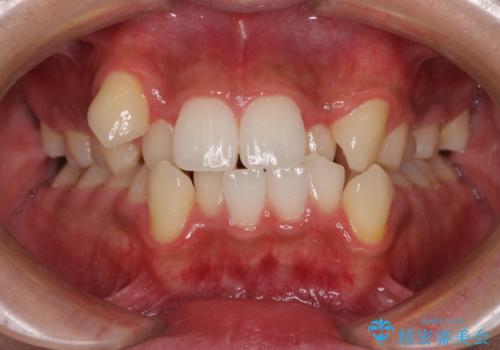

上下の八重歯とクロスバイト ワイヤー装置での抜歯矯正

- 八重歯とクロスバイトを気にして来院された患者様です。

上下ともに八重歯が顕著であり、前歯のクロスバイトがあったため、上下左右の第一小臼歯4本を抜歯し、ワイヤー装置での抜歯矯正を行うこととしました。